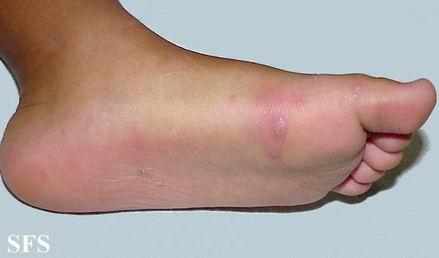

乐鱼手机站入口感染性疾病科主任李红兵,擅长感染性疾病诊治。李红兵主任说:“从临床表现上来说,手足口病发病快,部分患儿首先出现发热,或伴有咳嗽、流涕,因而早期很象感冒,随后开始出现皮疹,通常在手、足、臀部出现皮疹,口腔出现疱疹。多数患儿口痛明显,婴儿表现为流涎、拒食及哭闹,或被家长发现口内长疱;皮疹常见于手掌、脚掌和臀部,其次是膝盖、肘部。部分患儿仅有皮疹,而无发热。典型的皮疹是米粒大小的疱疹和红疹,疱疹周围可能会有红晕,大部分不痒不痛。皮疹多少跟病情轻重不成正比,临床上还观察到重症病例反而皮疹稀少。口腔疱疹,加上手心、足底及臀部任一处或一处以上出现上述皮疹,即可临床诊断手足口病,如在流行季节接触过手足口病患儿,可能性更大。不典型的手足口病又很容易和感冒、丘疹性荨麻疹、水痘混淆。”